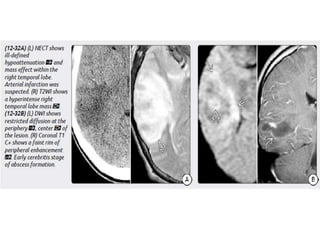

Abscess Abscess is initiatedby focal intracranial infection as an area of cerebritis and evolves into a collection of pus surrounded by a vascularized capsule. Size- 5 mm up to several centimetres. Age – most common in 3rd and 4th decades. Infants and neonates - its rare (may occur as complication of bacterial meningitis)

Location • Typically supra-tentorial,up to 14% infratentorial • Grey-White junction is common ( usually if hematogenous) • Subdural space • Frontal lobe – sinusitis, odontogenic infection • Temporal lobe - OM & mastoiditis • Multiple uncommon except in immunocompromised

4 stages ofevolution